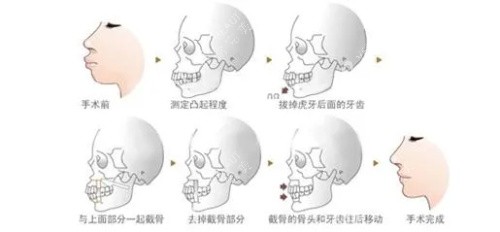

一、CBCT三维扫描:给骨头拍"3D电影",少看一眼都危险!

"医生说我上颌前突,可光看照片能准吗?"28岁的小李术前就犯了这个错。他只在普通X光片上看了骨头,结果手术时发现实际突度比影像多3毫米,差点造成面部神经损伤!

CBCT有多牛?它就像给骨头拍了部3D电影,能360度无死角显示:

上下颌骨的精细位置(误差<0.1mm)

牙根与神经管的"靠谱距离"

关节窝的形态是否正常

北京某综合医院口腔科主管张医师说:"没有CBCT就做正颌,相当于蒙眼开车。我们曾遇到患者CBCT显示双侧髁突不对称,及时调整了截骨方案,避免了术后张口受限。"